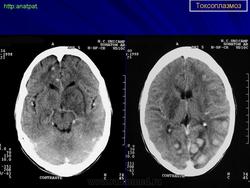

Церебральный токсоплазмоз.

Церебральный токсоплазмоз

Пато морфологи я. Патоморфологические изменения при приобретенном токсоплазмозе изучены в экспериментах на животных. Установлено, что в центральной нервной системе развиваются явления некротического перивентрикулита, мелкие очаги некроза в субкортикальном белом веществе. В сосудах головного мозга, мягкой мозговой оболочки и хориоидальных сплетениях отмечаются признаки серозно-пролиферативного воспаления. Обнаруживаются также глазные патологоанатомические изменения (типа ретинита, хориоидита, иридоциклита) и изменения во внутренних органах (сердце, легкие, печень, селезенка).

Врожденный токсоплазмоз чаще, чем приобретенный, приводит к летальному исходу. В головном мозге умерших обнаруживаются более или менее значительные очаги обызвествления, участки размягчения мозгового вещества, полости, заполненные жидкостью. Как правило, отмечается гидроцефалия, обусловленная воспалительной и рубцовой облитерацией водопровода среднего мозга, отверстий Люшка или других участков ликворных путей. Истон-чение вещества полушарий мозга может достигать степени их полного исчезновения.

Особенно характерна триада симптомов: хореоретинит, гидроцефалия, очаги обызвествления в головном мозге. Кроме того, отмечаются менингеальные знаки, тонические и клонические судороги, парезы, параличи, олигофрения.

Дифференциальная диагностика изображения